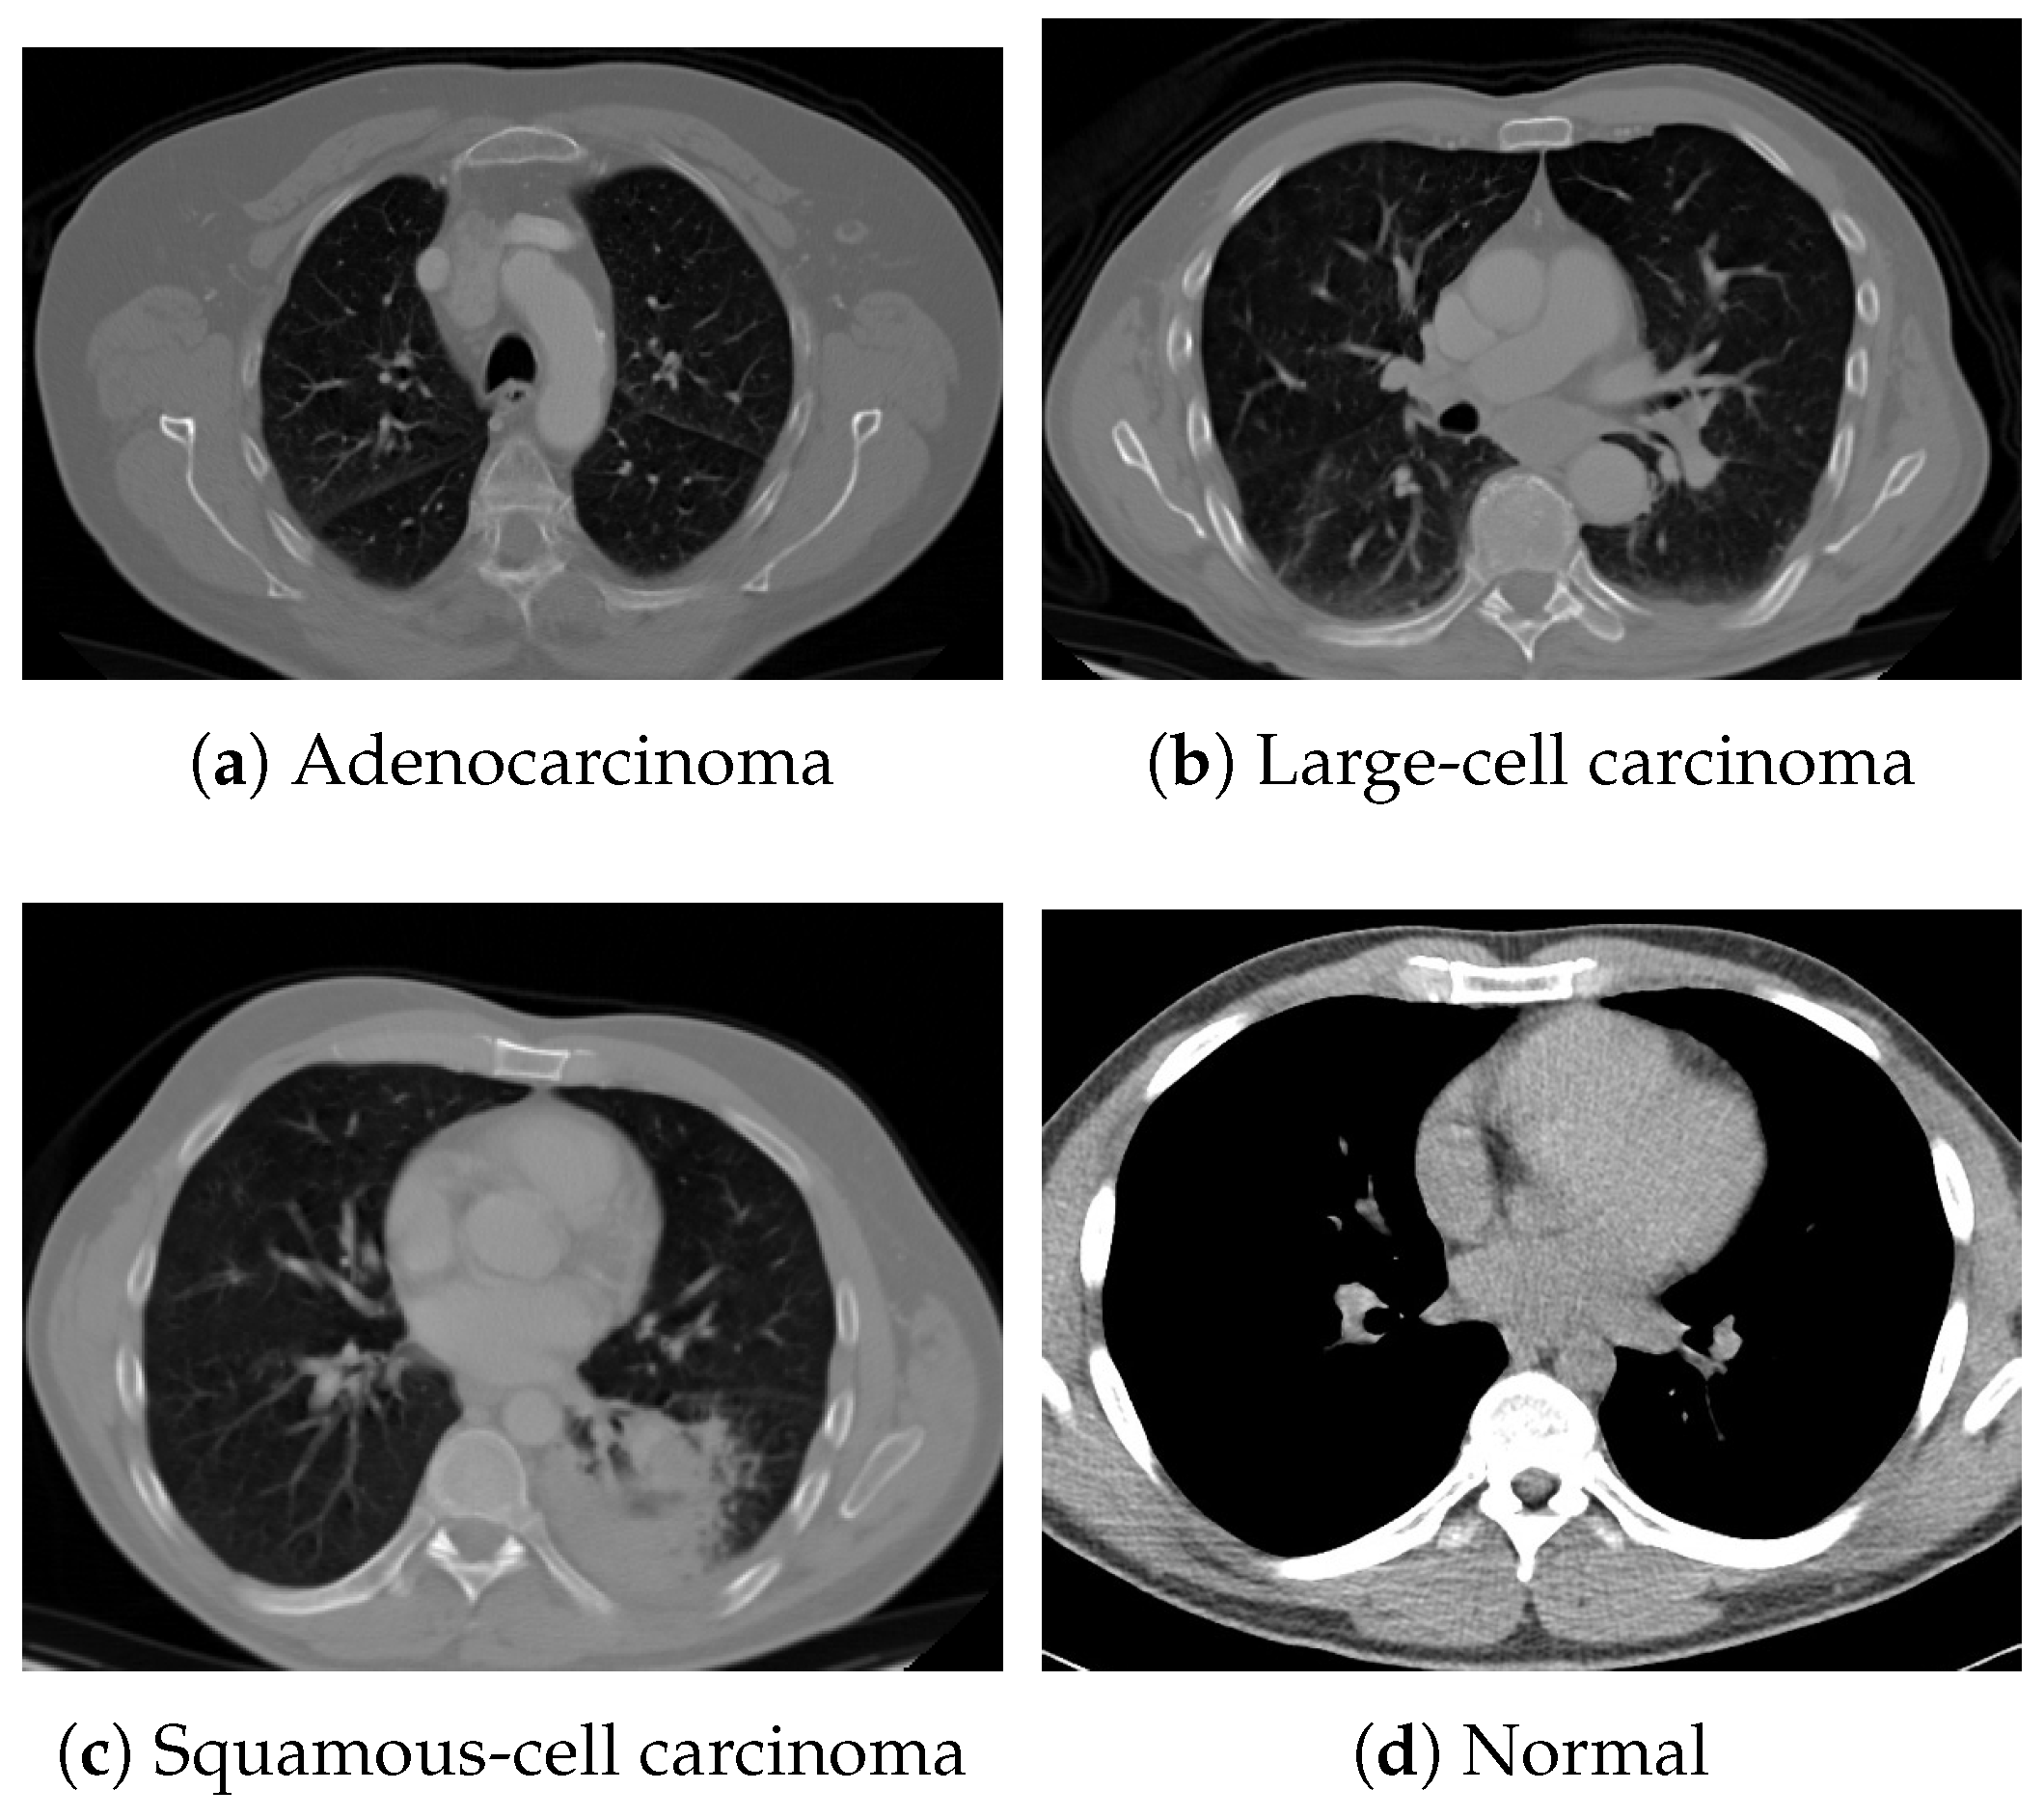

For pretraining, we utilized a subset of the J-MID (https://www.radiology.jp/j-mid/ (accessed on 6 April 2025)) database, which contains large-scale CT scans from Japanese medical institutions, and the RICORD dataset [58], an open dataset that was developed collaboratively by the Radiological Society of North America and international partners and contains chest CT scans collected from four countries. Each dataset was constructed with two domains based on mediastinal and lung window settings in chest CT images. Both domains are denoted as and , and the labels are not used during pretraining. Specifically, for the J-MID subset, (the mediastinal window) contains 31,256 CT images, and (the lung window) contains 26,403 CT images. The RICORD dataset comprises 12,897 (mediastinal window) images and 11,668 (lung window) images for pretraining. For the J-MID dataset, was generated using a window level (WL) of HU and a window width (WW) of HU, whereas was generated using a WL of HU and a WW of HU. For the RICORD dataset, was generated with a WL of HU and a WW of HU, while was generated with a WL of HU and a WW of HU. These parameter ranges were selected to cover clinically standard lung and mediastinal window settings while accommodating inter-scan variability in DICOM metadata. The corresponding images for each example are shown in Figure 2 and Figure 3. For fine-tuning and evaluation, we utilized two public datasets: the SARS-CoV-2 CT-Scan Dataset [59] and the Chest CT-Scan Images Dataset (https://www.kaggle.com/datasets/mohamedhanyyy/chest-ctscan-images (accessed on 6 April 2025)). Both datasets were used for the coronavirus disease 2019 (COVID-19) and chest cancer classification tasks, respectively. The data breakdown is as follows: the SARS-CoV-2 CT-Scan Dataset comprises 1589 training, 397 validation, and 495 test images, labeled into two (COVID-19 and Normal) classes. The Chest CT-Scan Images Dataset comprises 490 training, 123 validation, and 315 test images labeled into four (adenocarcinoma, large-cell carcinoma, squamous-cell carcinoma, and normal) classes. COVID-19 classification and lung cancer classification were selected as downstream tasks because chest CT is widely used in clinical practice for diagnosing both COVID-19 and lung cancer, allowing for an evaluation that closely reflects real-world clinical scenarios. Accordingly, to ensure reproducibility and enable fair comparisons with prior studies, we prioritized the use of publicly available datasets. The corresponding images for each example are shown in Figure 4 and Figure 5.

Figure 4.

Examples of chest CT images on the SARS-CoV-2 CT-Scan dataset: (a) COVID-19 and (b) Normal.

Figure 5.

Examples of chest CT images from the Chest CT-Scan Images dataset: (a) adenocarcinoma, (b) large-cell carcinoma, (c) squamous-cell carcinoma, and (d) normal.